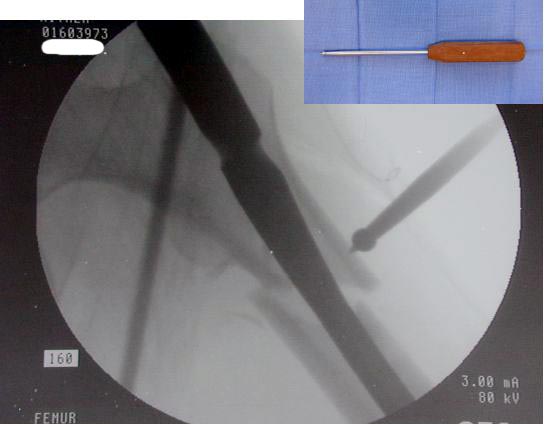

Большие преимущества у интрамедуллярных штифтов, метод хорош и можно произвести из минимального доступа, но во время операции необходимо контролирование варуса, затем приступить к блокированию.

Контролировать варус

Ap pelvis Rt sub-intra trochanteric Fracture, AP Rt hip, Postop Blade Fixation